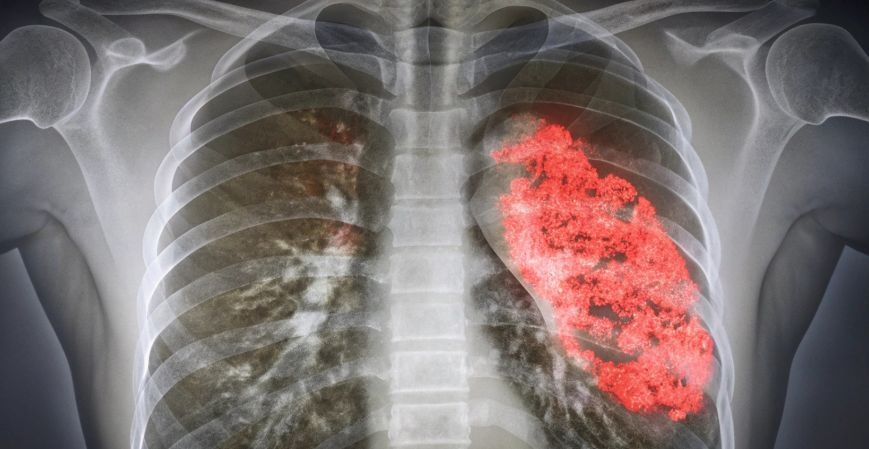

The Fungal Pneumonia Epidemiology Forecast explores the evolving patterns, prevalence, and management of fungal pneumonia across diverse populations and healthcare systems. Fungal pneumonia is a respiratory infection caused by fungi such as Aspergillus, Cryptococcus, or Pneumocystis jirovecii, often affecting individuals with weakened immune systems or chronic lung conditions.

The significance of the fungal pneumonia market extends beyond clinical treatment—it highlights a growing public health concern linked to emerging fungal infections, antimicrobial resistance, and the rise in immunosuppressive conditions. As global health systems face complex respiratory challenges, fungal pneumonia represents an area requiring continuous surveillance and improved diagnostic capacity.